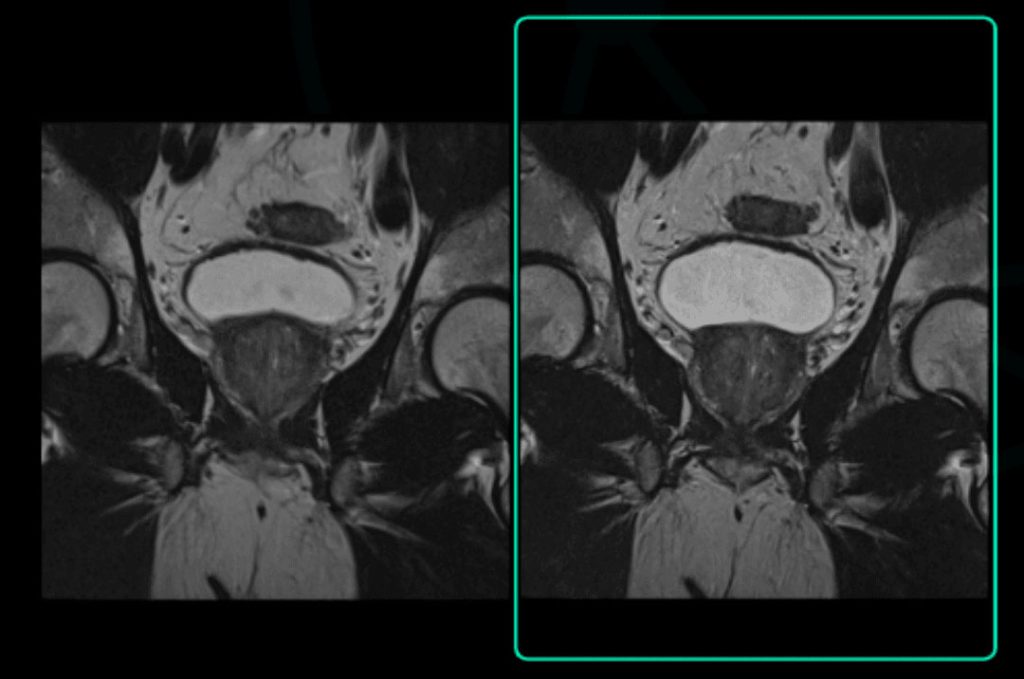

Varredura original: 3:39

Tempo Acq: 320×320

Varredura acelerada aprimorada por SubtleMR™

Tempo Acq: 2:09